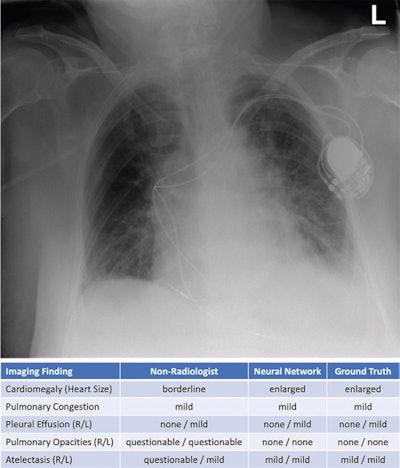

Exemplary bedside chest radiograph in which the initial grading of specific imaging findings by the physicians in the intensive care unit (nonradiologist) was not aligned with the grading by the experienced radiologists (majority vote) in an 85-year-old woman after pacemaker implantation for atrioventricular block 3. L = left patient side, R = right patient side. Image courtesy of Radiology.Next, a separate internal test set of 100 radiographs from 100 patients was assessed independently by a panel of six radiologists to establish ground truth for each exam. The team then used the kappa measure to compare these individual assessments, as well as those rendered by two ICU nonradiologist physicians using the neural network and by the neural network alone.

The neural network showed strong agreement with the majority vote of the radiologist panel (kappa, 0.86) -- a performance higher than the agreements of the individual radiologists with ground truth information (average kappa, 0.81).

In addition, with access to the results from the neural network when rating the radiographs, both of the ICU physicians improved their agreement with ground truth from 0.79 to 0.87 (p < 0.001), which was slightly higher than the agreement achieved by each unaided radiologist alone, the researchers reported.